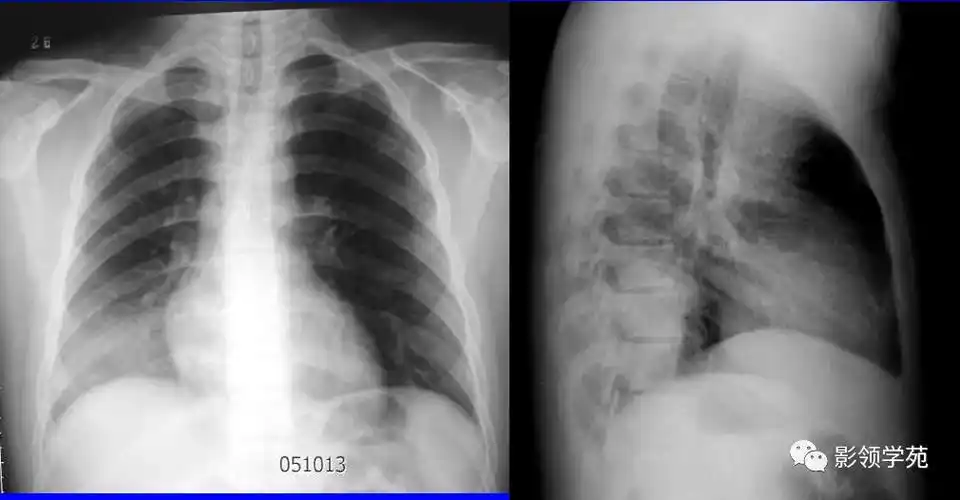

病例 1:同一小叶性肺炎患者于同日拍摄的胸片和肺 ct.

沿肺纹理有模糊的斑片状阴影.肺纹理增粗,模糊.x线表现